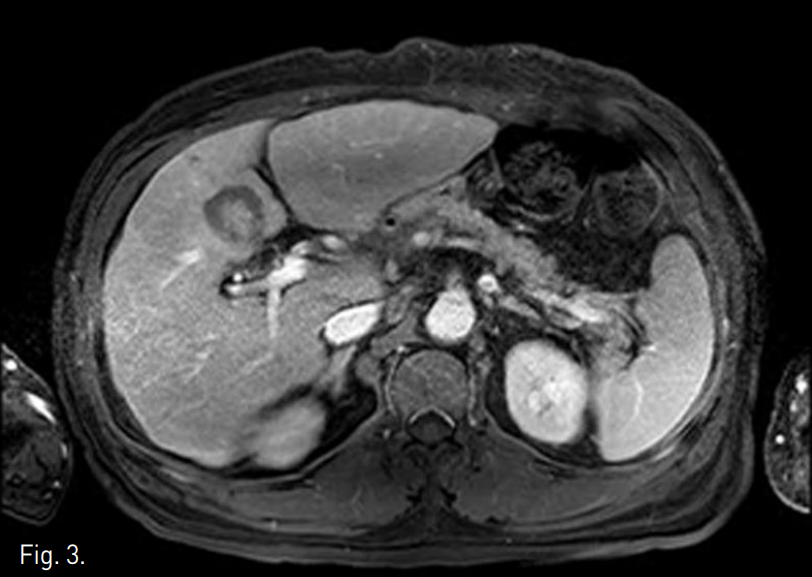

TACE중 실시한 CT during hepatic arteriography (CTHA) (Fig.1A)와 간동맥조영술(Fig.1B)에서 S4의 병변이 저혈관성의 종괴로 보인다. TACE이후 시행한 lipiodol CT 에서 lipiodd의 침착이 충분하지 않았다(Fig.1C).

A. CTHA shows a hypovascular mass (arrow) at hepatic segment IV.

B. Subsegmental angiogram of S4 shows faint arterial supply to the tumor (arrow).

C. Lipiodol CT taken one day after TACE shows minimal lipiodol uptake at S4 HCC (arrow).

4F Yashiro catheter (Terumo, Japan)를 이용한 간동맥조영술에서 faint tumor staining이 관찰되었고 이어 시행한 CTHA에서도 병변이 저혈관성 종괴로 보였다. 2F Progreat catheter (Terumo, Japan)와 Fathom (Boston scientific, USA) 유도철사로 종양혈관을 superselection 하고 Adriamycin 15mg과 lipiodol 2.3cc mixture를 이용하여 chemoembolization을 시행하였다.

시술 다음날 시행한 lipiodol CT에서 S4의 HCC에 lipiodol이 충분히 침착되어 있지 않아 추가적인 국소 소작치료를 계획하였다.